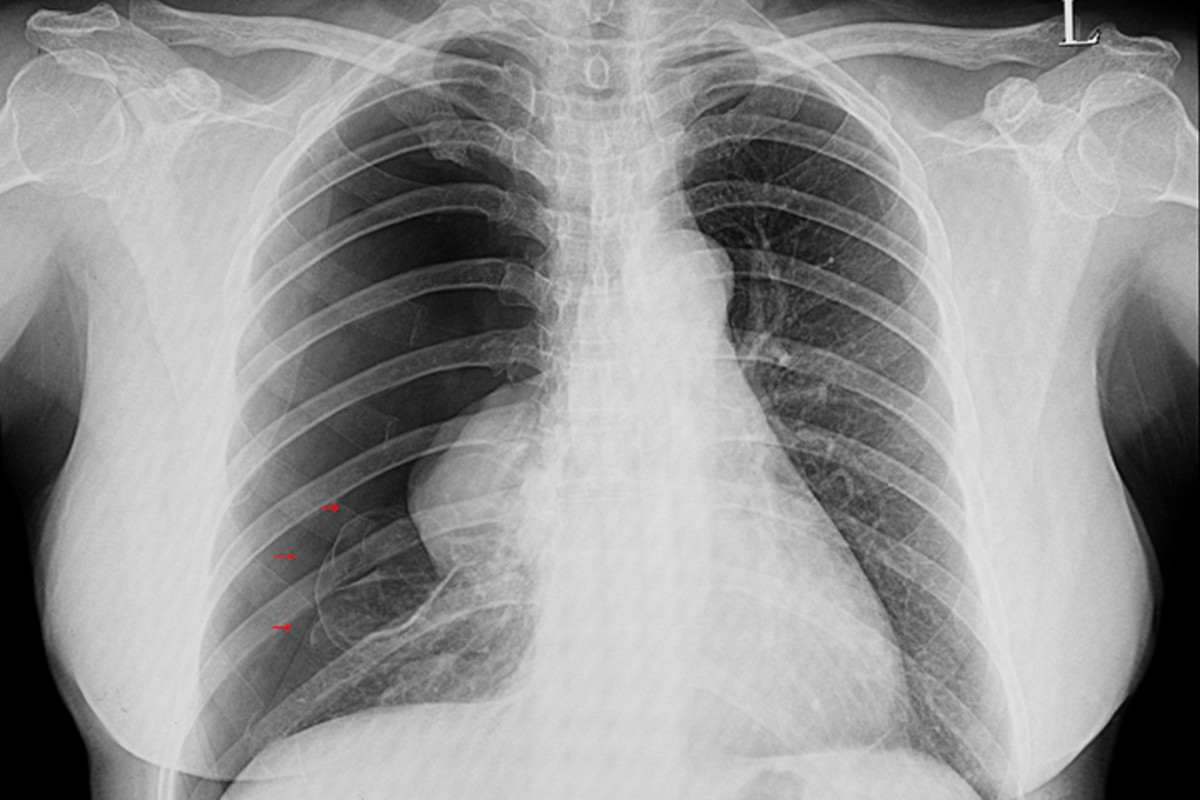

Normal bir göğüs röntgeni, COVID-19'dan kaynaklanan kalıcı solunum semptomlarıyla uğraşan hastalar için sadece az bir miktarını ortaya çıkarabilir. İki boyutlu taramalar, koronavirüsten kaynaklanan risk altındaki akciğer fonksiyonunu tam olarak ayırt edemez. Bu tanı için bilgisayarlı tomografi (BT) taraması adı verilen daha pahalı ve üç boyutlu (3D) olan ayrı bir teknik gereklidir.

Ancak bu durum yakında tamamen değişebilir. Yeni bir çalışmada, Iowa Üniversitesi'ndeki bilim insanları tarafından karşılaştırmalı öğrenme modeli adı verilen yeni bir saptama projesi geliştirildi. Bu yeni model, 3D BT görüntülerinden oluşturulan kompozit 2D görüntüleri kullanarak COVID-19 hastalarında riskli akciğer fonksiyonunun nasıl tespit edileceğini gösterir. Transfer öğrenme adı verilen başka bir teknik ise daha sonra bir BT taramasından akciğer diyagnostik bilgilerini bir göğüs röntgenine aktarır. Böylece göğüs röntgeni ekipmanının, sanki bu hastalar bir BT taraması kullanmış gibi anormallikleri tespit etmesine olanak tanır.

Frontiers in Physiology dergisinde yakın zamanda yayınlanan çalışmada araştırmacılar, karşılaştırmalı öğrenme modellerinin, COVID-19 hastalarında akciğer fonksiyonunun erken bir aşaması olan küçük hava yolları hastalığını tespit etmek için nasıl uygulanabileceğini gösterdiler. COVID-19 hastalarının modelleri, küçük hava yolları hastalığı olanları daha ileri solunum sorunları olanlardan ayırarak, tehlikeye giren akciğer fonksiyonunun ciddiyetini ayırt edebiliyordu.